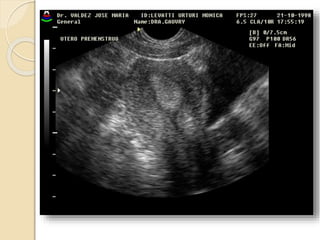

FIBROMA O LEIOMIOMA UTERINO

Patología común del útero que ocurre aproximadamente

en el 40% de las mujeres mayores de 35 años.

Los fibromas habitualmente son múltiples y más

comúnmente asintomáticos.

Se clasifican en:

• Submucosos: son los menos frecuentes pero es mas

probable que produzcan síntomas.

• Intramurales: Es el tipo mas común.

• Subserosos: Con frecuencia son pediculados y

pueden simular masas anexiales.